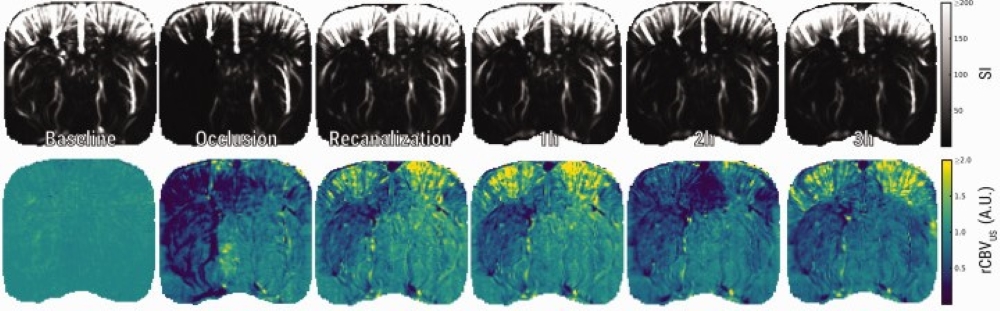

Ultrafast ultrasound (fUS) and dynamic susceptibility contrast-enhanced MRI (DSC-MRI) offer powerful, non-invasive tools to track cerebral blood volume (CBV) dynamics in experimental stroke. Here, these two modalities are used to explore hemodynamic changes before, during, and after middle cerebral artery occlusion (MCAO) in rats. With ultrasensitive Doppler and ultrafast localization microscopy, fUS captures CBV and flow velocity (CBFv) in real time, while DSC-MRI provides a well-established benchmark for perfusion imaging. Both techniques reveal a transient hyperperfusion after recanalization, followed by incomplete CBV recovery and gradual decline in the lesion zone. Notably, discrepancies during occlusion highlight the unique signal properties and processing algorithms of each method. By combining fUS and DSC-MRI, researchers gain complementary, whole-brain insights into post-stroke hemodynamics, advancing preclinical stroke research.

Fig. Ultrasensitive Doppler shows loss and subsequent incomplete restoration of CBV after tMCAO. (a) Representative images of raw ultrasensitive Doppler signal and relative CBV (rCBVUS) over the course of an experiment.Ultrasensitive Doppler shows loss and subsequent incomplete restoration of CBV after tMCAO. (a) Representative images of raw ultrasensitive Doppler signal and relative CBV (rCBVUS) over the course of an experiment.